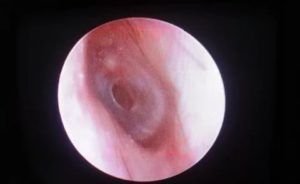

- Отоскопия. Исследуется сама барабанная перепонка и состояние краев дефекта (омозоленности, сращения с медиальной стенкой).

Разрыв тимпанической мембраны легко установить с помощью отоскопии — диагностической неинвазивной процедуры осмотра слухового прохода.

При разрыве барабанной перепонки отоскопия позволяет оценить состояние меатуса, собственно барабанной перепонки и, в ряде случаев, структур среднего уха.

Для ее проведения используют ушные воронки и лобный рефлектор или современный отоскоп, который совмещает в себе ушную воронку, источник света и увеличительный прибор.

Чтобы барабанная перепонка стала доступной для осмотра, необходимо предварительно очистить слуховой проход от серы, грязи, крови, выделений или инородного тела. При отоскопии определяются:

- усиление сосудистого рисунка при небольшом травмировании;

- кровоизлияния в мембрану при акустических травмах;

- видимые дефекты при значительных повреждениях;

- место разрыва с неровными краями, а также внутреннюю стенку барабанной полости;

- гематому тимпанической полости.